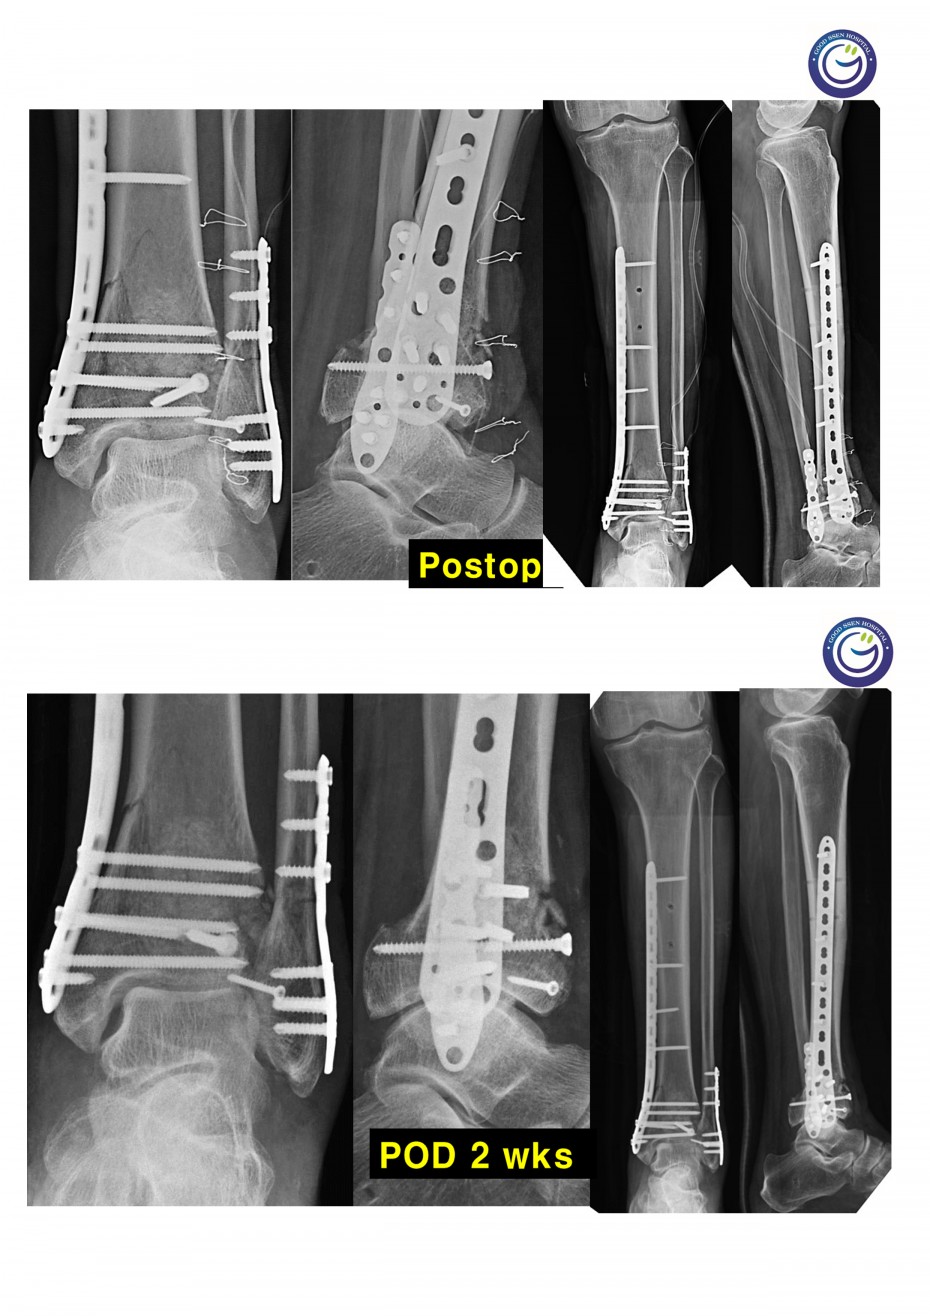

관절을 침범하는 심한 분쇄골절